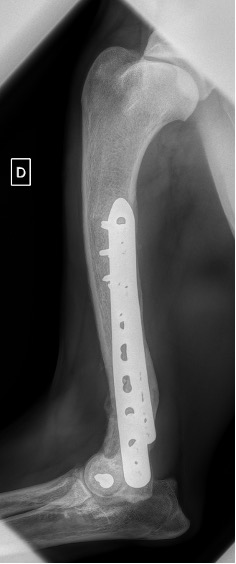

Notre préférence va vers le placement de deux plaques humérales : une médiale de la plus grande taille possible et l’autre latérale, généralement d’une taille inférieure à la première. Dans l’exemple 1 (chat européen), une plaque de 2 mm est utilisée médialement et une plaque de 1,5 mm latéralement. Dans l’exemple 2 (chien Malinois), une plaque de 3,5 mm est utilisée médialement et une plaque de 2,7 mm latéralement.

Exemple 1 :

Figure 2 : Post-Op Immédiat